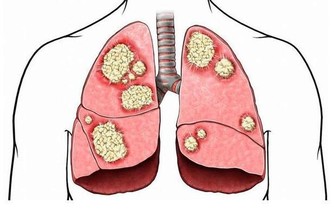

造成25至60歲年齡層失明常見原因就是糖尿病視網膜病變,罹患糖尿病十年以上,占三分之一都會出現視網膜病變;新竹台大醫院眼科醫師何奕瑢指出,主要是因長期處於血糖濃度高,當微血管出現缺氧現象,就會產生新生血管因子,若嚴重至演變非增生性視網膜病變,這時應盡快接受全視網膜雷射治療。

何奕瑢醫師進一步說明,糖尿病不但容易演變新生血管型青光眼、白內障、視神經病變等病症,也可能合併黃斑部水腫,但若白內障嚴重,不建議進行手術治療,因為反增加手術風險,加上血糖未控製良好,這時若開刀治療,恐會加速視網膜病變急速惡化,因此最好的方式還是積極控製好血糖後,再進行手術治療,並且進一步檢查和治療視網膜病變。